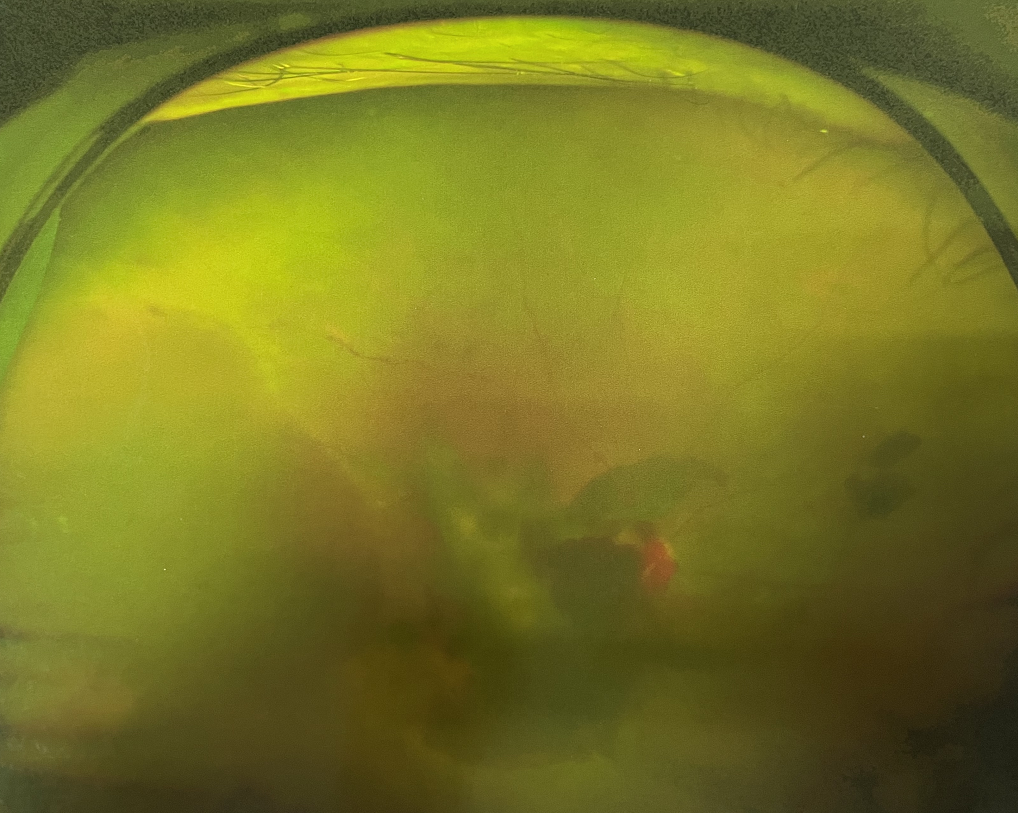

糖尿病視網(wǎng)膜病變是糖尿病在眼部的主要并發(fā)癥,是我國四大致盲眼病之一,主要以視網(wǎng)膜血管改變?yōu)椴±硖卣?。眼底多表現(xiàn)為視網(wǎng)膜出血、滲出、新生血管及增殖膜形成,嚴重威脅患者的視覺健康。

糖尿病視網(wǎng)膜病變患者早期可能沒有明顯的視力下降,有些患者因為玻璃體出血會出現(xiàn)突然視力下降,晚期患者視力多有明顯下降。

糖尿病視網(wǎng)膜病變可分為六期:

?、衿冢河形⒀芰龌虿⒂行〕鲅c。

?、蚱冢河悬S白色“硬性滲出”或并有出血斑。

?、笃冢河邪咨?ldquo;軟性滲出”或并有出血斑。

?、羝冢貉鄣子行律芑虿⒂胁Aw積血。

?、跗冢貉鄣子行律芑虿⒂欣w維膜增生。

?、銎冢貉鄣子行律芑虿⒂欣w維膜增生,并發(fā)視網(wǎng)膜脫離。